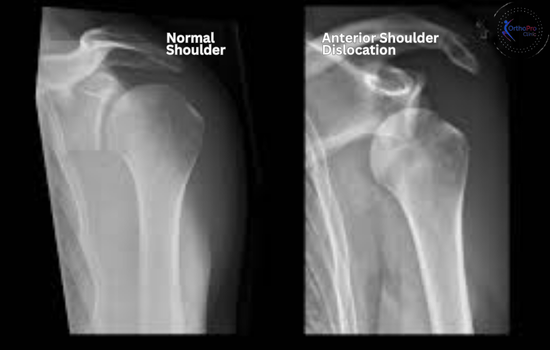

Anterior shoulder dislocation is a form of shoulder injury where the humerus head or upper arm bone displaces forwards from its typical position in the shoulder socket.

This dislocation accounts for approximately 95 % of all shoulder dislocations and often results from a forceful external rotation or abduction movement.

- Bone Structures: Severe dislocations may cause fractures in the humeral head or glenoid cavity, visible on an anterior shoulder dislocation X-ray.

- Anterior Shoulder Dislocation X-ray: Identifies dislocation and bone damage.